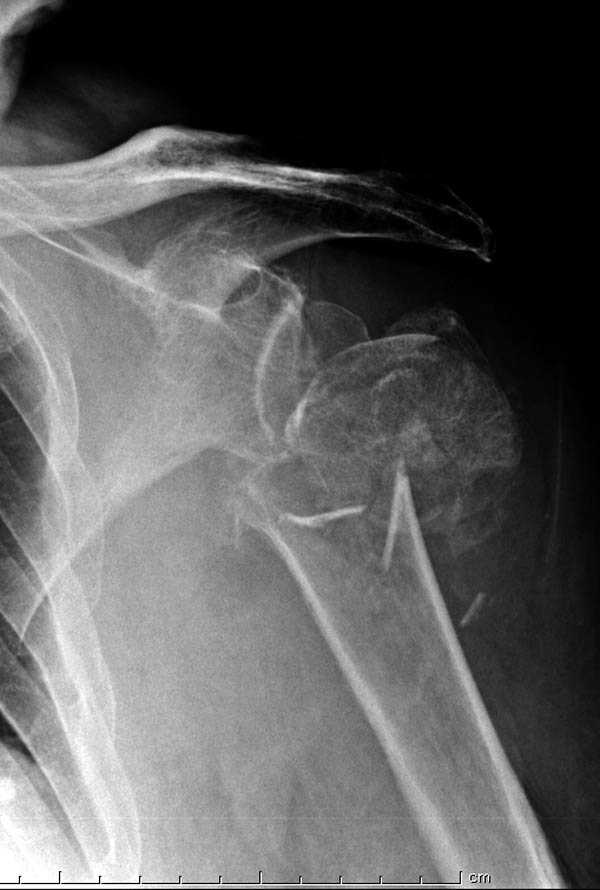

Здесь пример открытой репозиции 57 летнего с переломом плеча (1,2) смещение обнаружено на интероперационном снимке. При нормальной прямой проекция (3) угловое смещение обнаружили в аксиальной проекции (4)